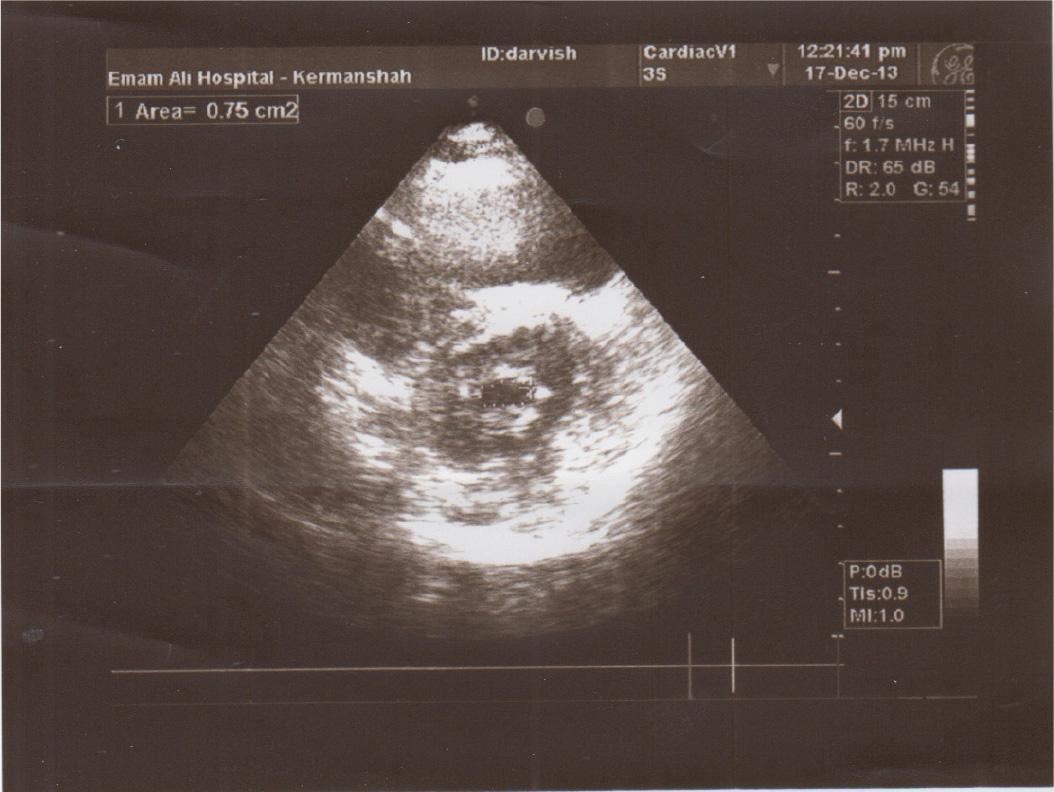

Figure 1

Clot free in the left atrium.